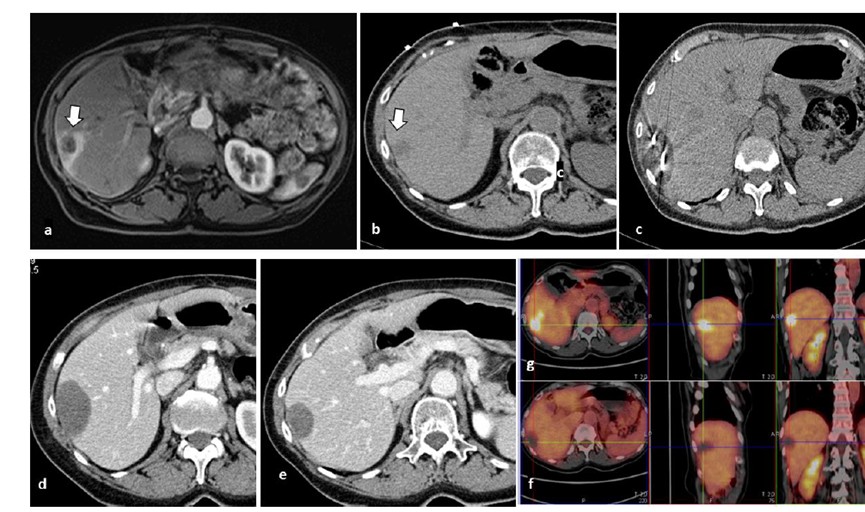

冷凍消融膽囊附近腫瘤病灶

(A)動(dòng)脈期 MRI 顯示膽囊附近有外周增強(qiáng)病變(箭頭)。

(B)手術(shù)過程中 CT 顯示冷凍探針位于病灶內(nèi)。

(C)消融后,術(shù)后 1 個(gè)月CT 顯示完全消融(箭頭)。

(A)動(dòng)脈期CT圖像顯示有一個(gè)包膜下結(jié)節(jié)(箭頭)。(B)門靜脈期CT圖像顯示病灶區(qū)(箭頭)。(C) 在手術(shù)過程中的CT顯示一個(gè)冷凍探針位于病灶內(nèi)。(D)消融后,術(shù)后1個(gè)月影像CT顯示完全消融。患者在手術(shù)及住院期間無并發(fā)癥及重大并發(fā)癥發(fā)生。隨訪時(shí)間中位數(shù)為7個(gè)月(范圍:3-12個(gè)月),隨訪期間患者無局部腫瘤進(jìn)展或死亡。

技術(shù)成功率為100%,本研究中77.8%(7/9)的患者達(dá)到了完全消融,輔助局部治療后,所有患者均完全消融。

膽囊附近轉(zhuǎn)移灶(來自子宮頸癌)的冷凍消融術(shù)(A)門靜脈期 CT 圖像顯示膽囊附近有病變(箭頭)。(C) 手術(shù)過程中CT 顯示冷凍探針位于病灶內(nèi)。(D)消融手術(shù)后 1 個(gè)月CT 顯示完全消融。